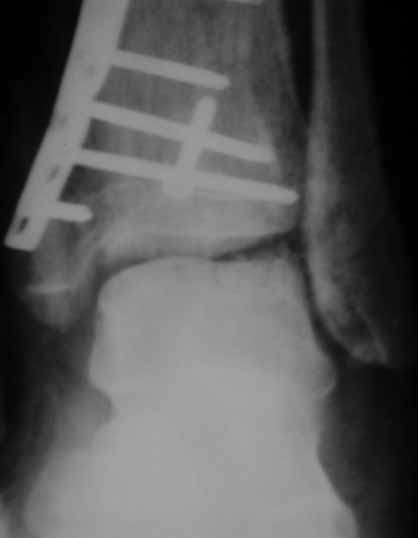

Отчет по "пилону":)))

Извиняюсь пропал - оперировал "пилон". В форуме не хотел обсуждать финансовые возможности пациента. Потянул комбинированную пластину. Опыт общение с пластиной "крест" есть - не очень понравилось - слишком много места занимает, даже с учетом обрезаний лишнего. Сделал доступ огибающий медиальную лодыжку спереди. В переднем крае оказался достаточно крупный отломок - удалось зафиксировать винтом. Дефекта кости не оказалось.

Какой таран? в одном сегменте повреждается одно или другое. Крайне редко обе части. Анатомическая репозиция безукоризненна,но для чего межфрагментарный винт при использовании LCP это очевидное нарушение методики. А по поводу Мальтийского креста, то это оличный незаменимый, в ряде случаев, фиксатор, но не для этого перелома, абсолютно!С Уваением! Сергей.